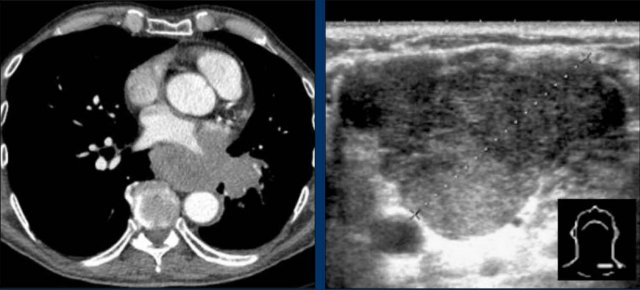

Pericardial effusion

When encountering an enlarged cardiac silhouette on chest radiography, it is essential to consider pericardial effusion as a potential mimic of cardiomegaly.

Case Example 1: Pericardial Effusion Mimicking Cardiomegaly

- On the chest radiograph, the patient appears to have a dilated heart.

- However, CT imaging clearly demonstrates that the apparent enlargement is due to significant pericardial fluid accumulation, not true myocardial chamber enlargement.

Postoperative Pericardial Hemorrhage

In patients with recent cardiac surgery, a sudden change in heart size on chest X-ray should raise suspicion for pericardial bleeding, which may be life-threatening.

Case Example 2:

- A postoperative patient showed a change in the cardiac silhouette.

- Echocardiography detected only a minimal pericardial effusion.

Case Example 2 - CT imaging

- CT imaging revealed a large posterior pericardial effusion compressing the left ventricle (blue arrow: effusion; red arrow: compressed, contrast-filled left ventricle).

- Surgical exploration confirmed a large posterior pericardial hematoma.

Note: Minimal anterior fluid on ultrasound may underestimate the true volume if the effusion is loculated posteriorly, highlighting the value of CT in postoperative cases.